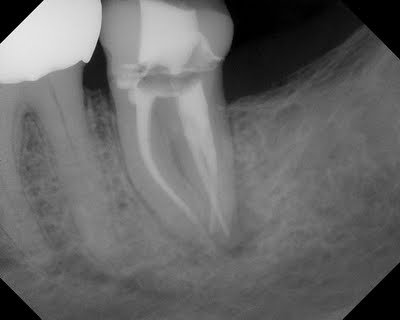

This patient came to SSE for emergency treatment. #18 DX: Necrotic pulp w/ Symptomatic Apical Periodontitis. RCT initiated. 3 canals located, however a 4th distal canal is not found. 2 distal roots are apparent the pre-op film. The ML, MB and a distal canal are located. The distal is opened looking for the 4th canal. After 20-30 minutes of searching for 4th canal, the patient is re-appointed for 2 step treatment.

With these images, the 4th canal is easily located within minutes of opening the tooth.